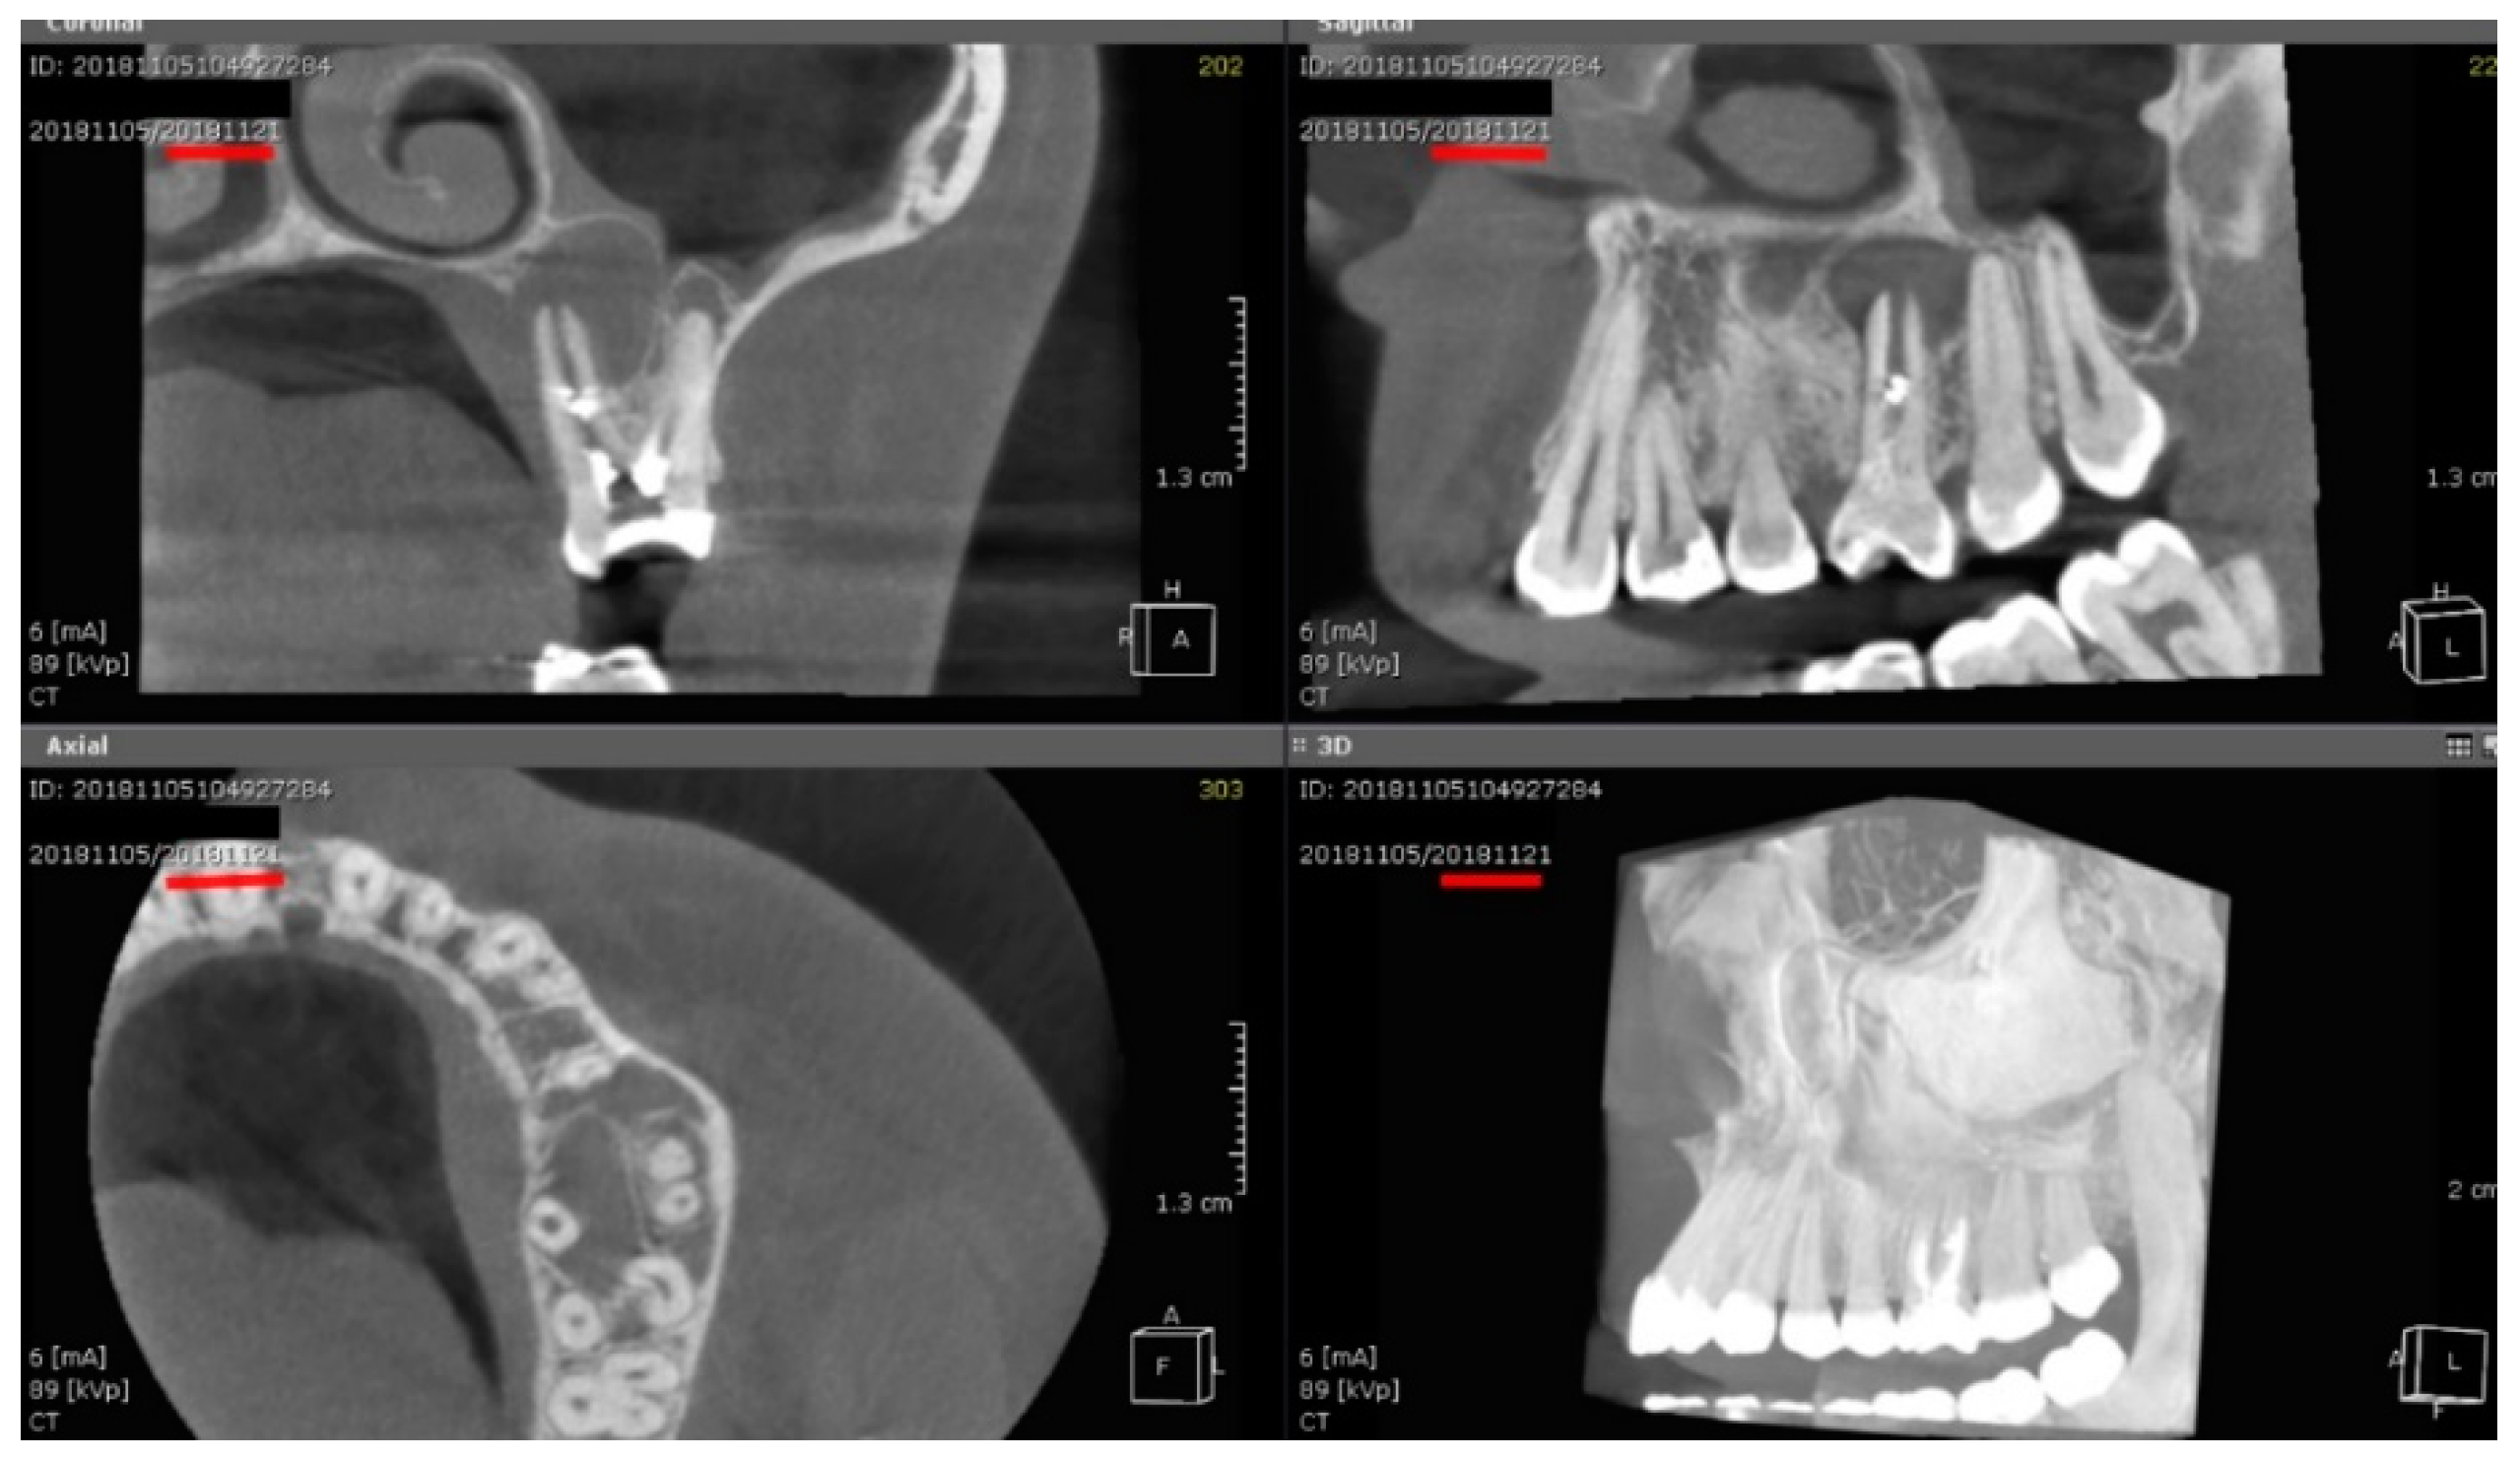

Figure 1 presents CBCT images (coronal, sagittal, and axial views) of a patient with a cystic granuloma treated using the experimental protocol, showing near-complete lesion resolution and bone regeneration at the 2-year follow-up.

Figure 1. CBCT Views Illustrating a Maxillary Cystic Lesion and Healing Outcome: Coronal, Sagittal, and Axial Slices at Baseline, with 3D Reconstruction Showing Bone Regeneration at the 2-Year Follow-Up.